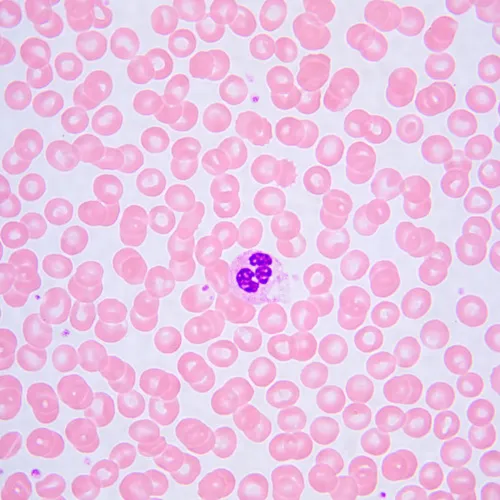

The microscope is suitable for observing transparent and translucent biological samples, such as smears and cross sections using the brightfield microscopy technique in transmitted light. The coded revolving nosepiece maintains a comfortable brightness level when the objectives are changed. The microscope's intelligent lighting control system improves comfort and speed of the researcher’s everyday work. Smart features help students ease into the profession and gain the professional experience they need. Practical aspects play an important role for student microscopes. The size, weight, ease of storage of the cords, and the microscopes themselves are important in everyday use. This microscope is convenient to move around on a table due to its small dimensions and low weight. It does not take up much space in storage. It is equipped with a 2MP camera with an HDMI interface. The digital camera outputs the image directly on the monitor screen with no connection to a computer. The software complements the system with analysis and documentation functions. The monitor in the digital microscope has Full HD resolution.

- Observations of transparent and translucent samples in brightfield in transmitted light